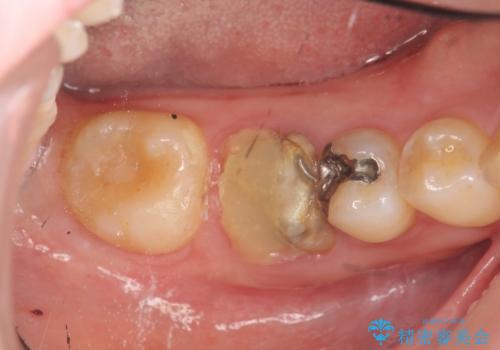

- 虫歯を数年放置した結果、痛みがひどくなり治療を希望され来院されました。

根だけ残った歯は、破折があり急性の炎症が認められ抜歯が必要な状態です。

抜歯後は、前後の歯を削らずにしっかりと咬合力を回復できるインプラント治療を選択されました。